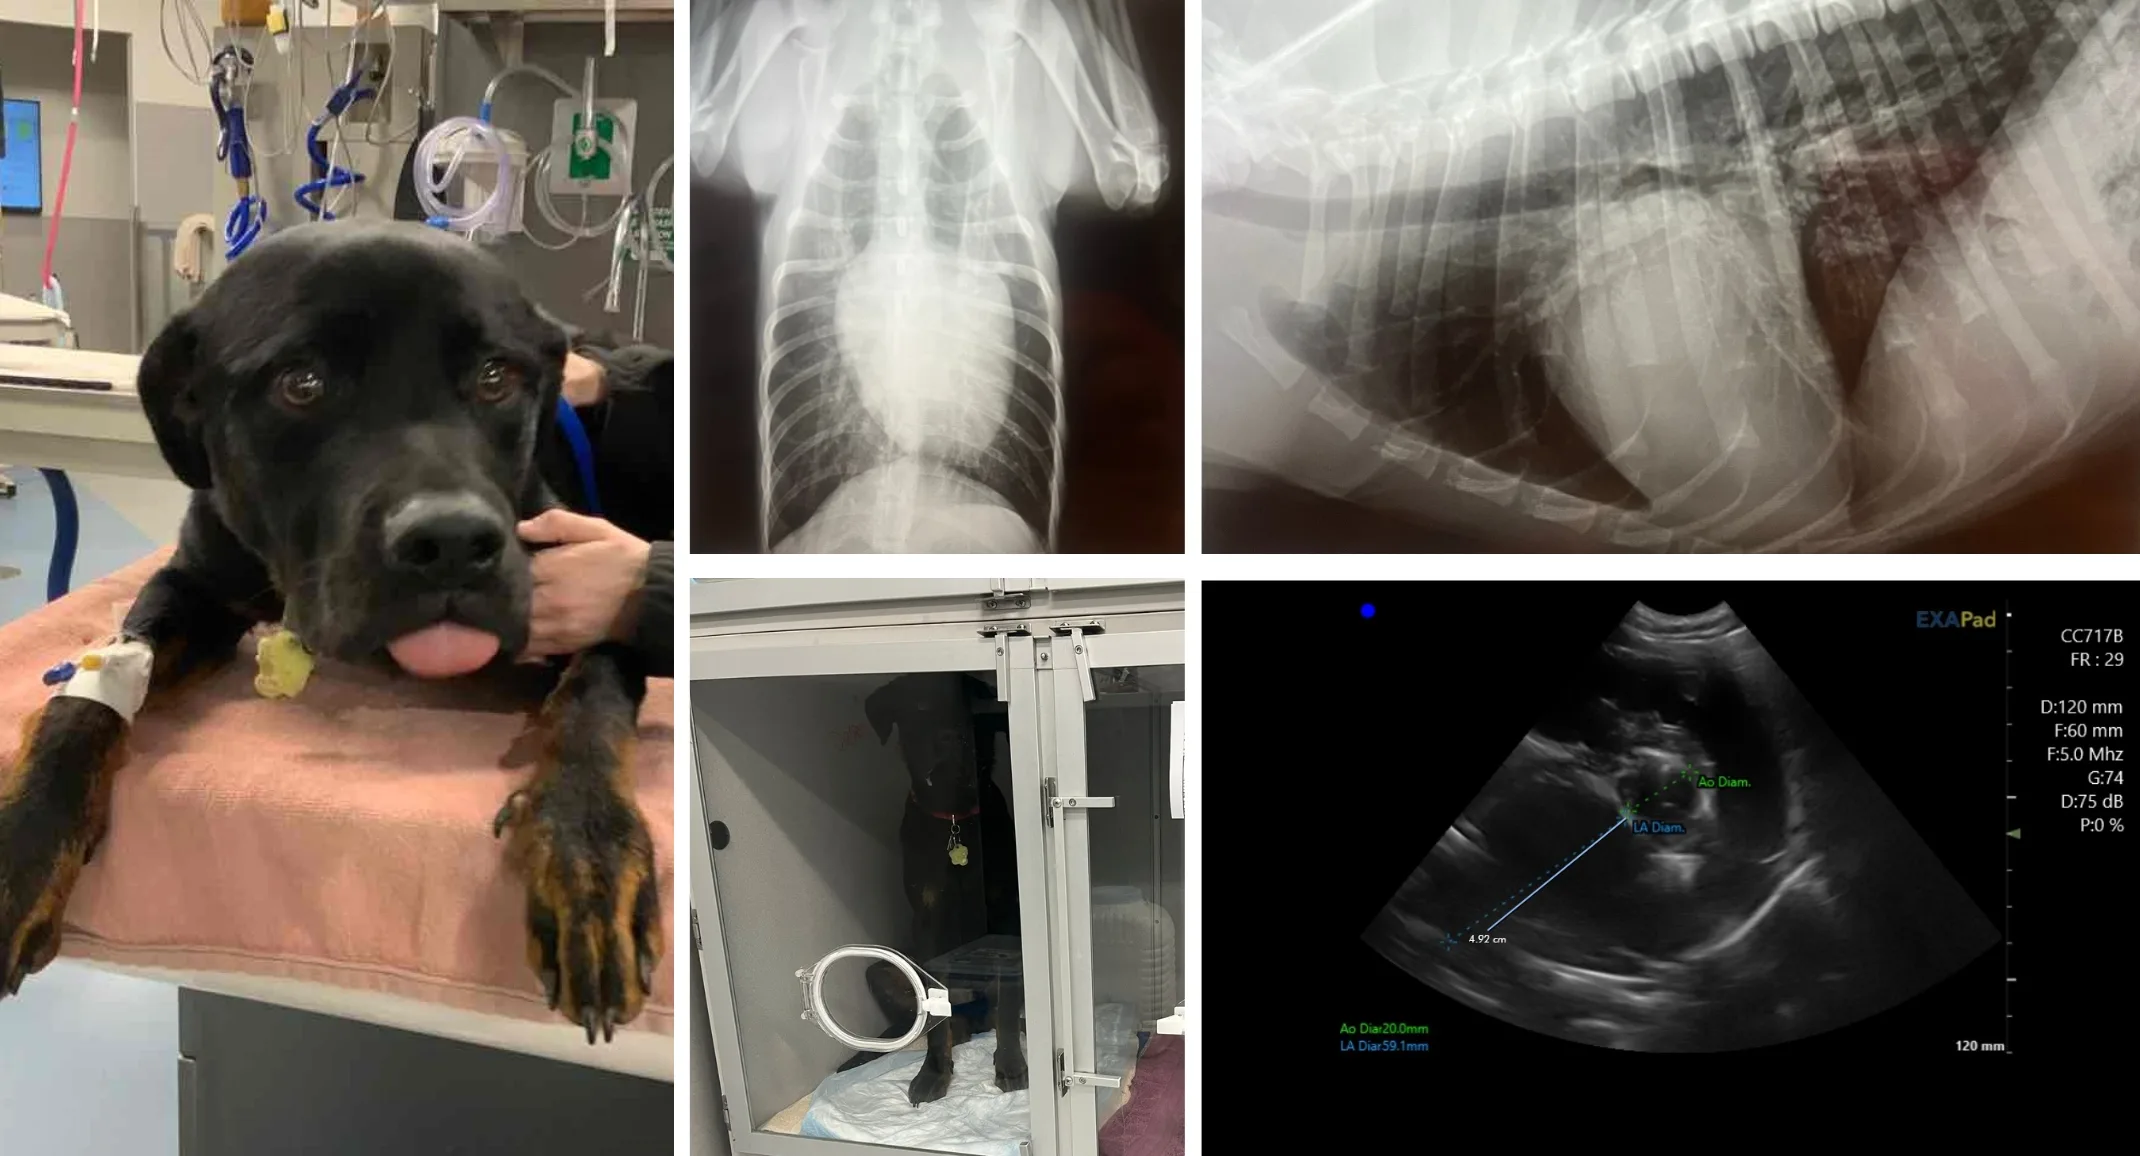

Roscoe, a 9-month-old Rottweiler, presented to his primary veterinarian when his owner noticed a strange breathing pattern. Upon presentation, Roscoe seemed to be breathing normally but the owners agreed to radiographs to be sure. While obtaining x-rays, Roscoe’s unusual breathing pattern started again. Radiologist interpretation alluded to cardiogenic changes that resulted in fluid buildup in the lungs. To further investigate this, an echocardiogram needed to be performed and Roscoe was placed on oxygen therapy. He was then referred to Veterinary Emergency and Specialty Hospital’s teleradiology service for an echocardiogram, performed by Dr. Brock Lofgreen and interpreted by a board-certified veterinary cardiologist. The specialist in cardiology provided a detailed report on the imaging, along with a diagnosis and treatment plan, including medication. In this case, Roscoe was diagnosed with dilated cardiomyopathy.